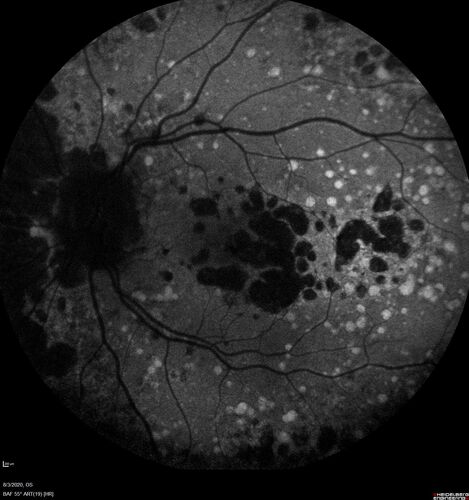

Age-related macular degeneration - Geographic Atrophy - Intermittent CME left eye from CRVO, Anemia, Diabetes

79 year old female - 3 years post CRVO in the left eye (20/32 VA) with intermittent CME.  Left eye is the better eye.  Vision is stable since 2 years ago

PMHx: Type II DM x 20 years, Chronic Anemia, Hyperlipidemia

VA 20/200 OD, 20/50 OS (usually 20/40)